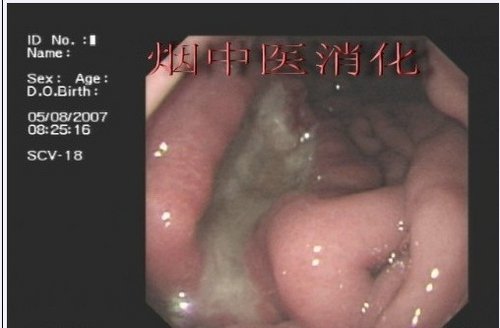

上述的两种表现集中体现在以下的病例中,此病人曾在其他医院诊断为“胃溃疡”,但我们看病灶的基底面和周围粘膜的表现,很明显的是一个“癌”的表现:

和上图为同一个病人:

而一个良性的胃溃疡,无论多么的大,多么的“不好看”,不会有粘膜集中像,边缘整齐,而且会有相对均匀的黑褐色血痂覆盖,也没有高低不平、硬感、暴露感的基底部:

最后给大家留一个考试题,根据上面所讲的观点分析下面的胃镜图片,分析过程和结果都正确的加2分,只答对结果而没有分析过程的不得分,为了避免提前加分可能会起到暗示作用,自发布之日起,一周后统一加分,